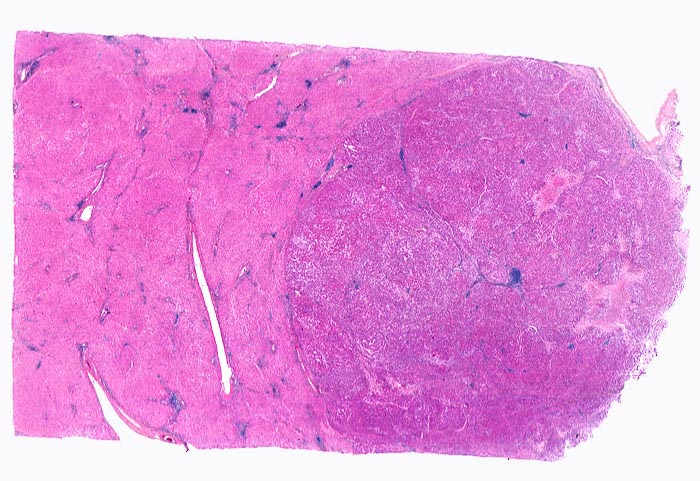

Morphologie: Makroskopisch imponiert das hepatozelluläre Karzinom als solitäre grosse Tumormasse, als zahlreiche zirrhoseartige Knoten oder als scharf begrenzter Knoten mit oder ohne Kapsel. Die tumorfreie Leber ist in der Mehrheit der Fälle zirrhotisch umgebaut. Mikroskopisch bilden die Tumorzellen mehr als 2 Zellen breite Trabekel ( 1237), kompakte Tumormassen ( 1229) oder pseudoglanduläre Strukturen (dilatierte Canaliculi) ( 1212)( 1199). Desmoplastisches Bindegewebe fehlt meist. Innerhalb des Tumors fehlen Portalfelder. Es finden sich lediglich Arterien. Etwa bei der Hälfte der Karzinome lässt sich intrazytoplasmatische oder intracanaliculäre Galle ( 1238) nachweisen. Immunhistochemisch lassen sich mit einem polyklonalen Antikörper gegen Carcinoembryonales Antigen (CEA) Gallecanaliculi zwischen den Tumorzellen nachweisen. Die Tumorzellen bilden keinen Schleim.

Innerhalb des Tumors Blutgefässe, aber keine Portalfelder.

Die Tumorzellen bilden Trabekel, welche überwiegend mehr als 2 Zellen breit sind und Pseudodrüsen.

Sinusoidartige Blutgefässe mit Endothelauskleidung verlaufen zwischen den Trabekeln und den Pseudodrüsen.

Tumorfreies Parenchym mit chronischer viraler Hepatitis (B und D): dichtes chronisches Entzündungsinfiltrat in den Portalfeldern übergreifend auf das Parenchym (Interfacehepatitis). Spärliche intralobuläre Entzündung mit Einzelzellnekrosen (Apoptosen). Fibrose der Portalfelder mit Septenbildung und unvollständigem zirrhotischem Umbau. Geringe gemischttropfige Verfettung des Leberparenchyms.